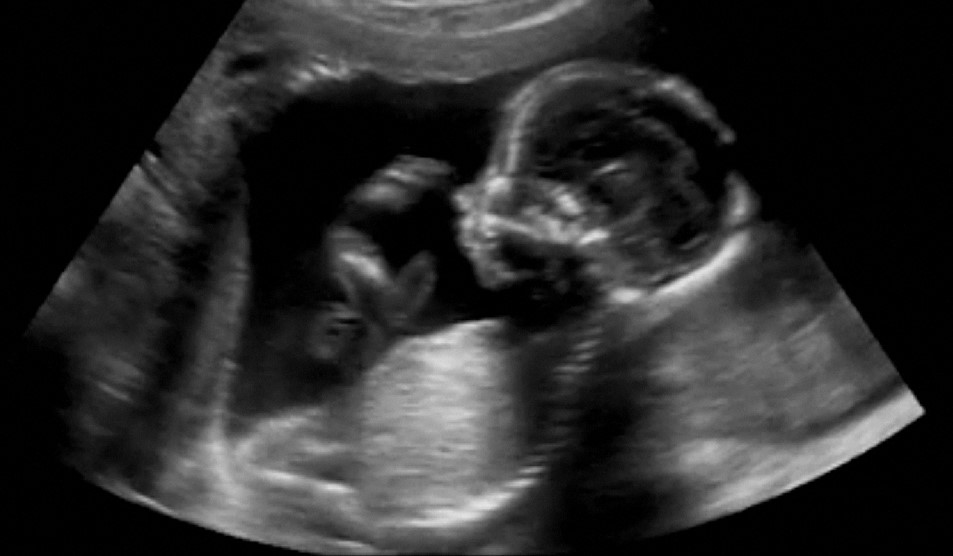

This is sometimes called a nuchal translucency scan . The nuchal translucency measurement can be taken during the dating scan . If you have agreed to have screening for Down's syndrome, the dating scan and the screening will usually happen at the same time . Find out more about the screening for Down's syndrome, Edwards' syndrome and Patau's syndrome . You will not be offered the combined screening test if your dating scan happens after 14 weeks .

an early pregnancy scan ( dating or booking scan ) between 11 and 14 weeks a mid pregnancy scan (also known as a fetal anomaly scan ) between 18 and 21 weeks You might also be offered a nuchal translucency scan (NT) at your early pregnancy scan to to find out how likely it is your baby may have either Down's syndrome, Edwards' syndrome or Patau . . .

About Non Invasive Prenatal Tests (NIPT, sometimes called Harmonyβ’ Test) and Nuchal Translucency (NT) Scans . Pregnant women in the UK are currently offered screening for trisomy 21 (Down Syndrome) at the first trimester Nuchal Translucency (NT) scan on the NHS . The NT measurement is undertaken with ultrasound and this measurement may be . . .